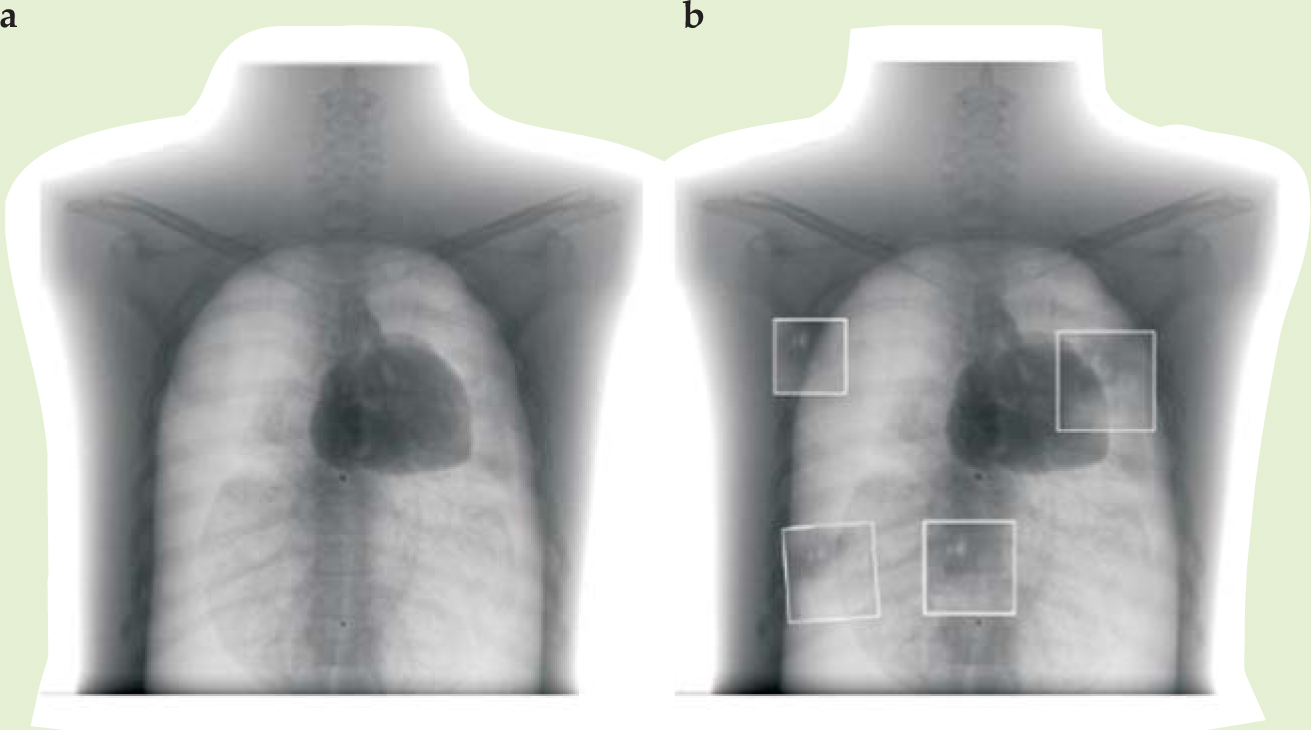

Rowlands envisions the XLV being useful at first for static imaging (in contrast to fluoroscopy) and chest x rays, an application well matched to the system’s dynamic range. He’s now exploring its clinical practicality at Canada’s Thunder Bay Regional Health Sciences Center in northwestern Ontario, where he is setting up a new imaging research institute. Figure 2 compares a standard digital radiograph of a phantom chest using an active-matrix system with some smaller patches using a prototype XLV; “phantom” here refers to a dummy body part that replicates absorption properties of human anatomy.

Figure 2. X-ray images of a phantom chest using (a) an active-matrix flat-panel imager and (b) an x-ray light valve, shown as boxed insets against the AMFPI chest x ray. Imperfections from the prototype x-ray light valve appear as artifacts in the image.

(Courtesy of John Rowlands.)